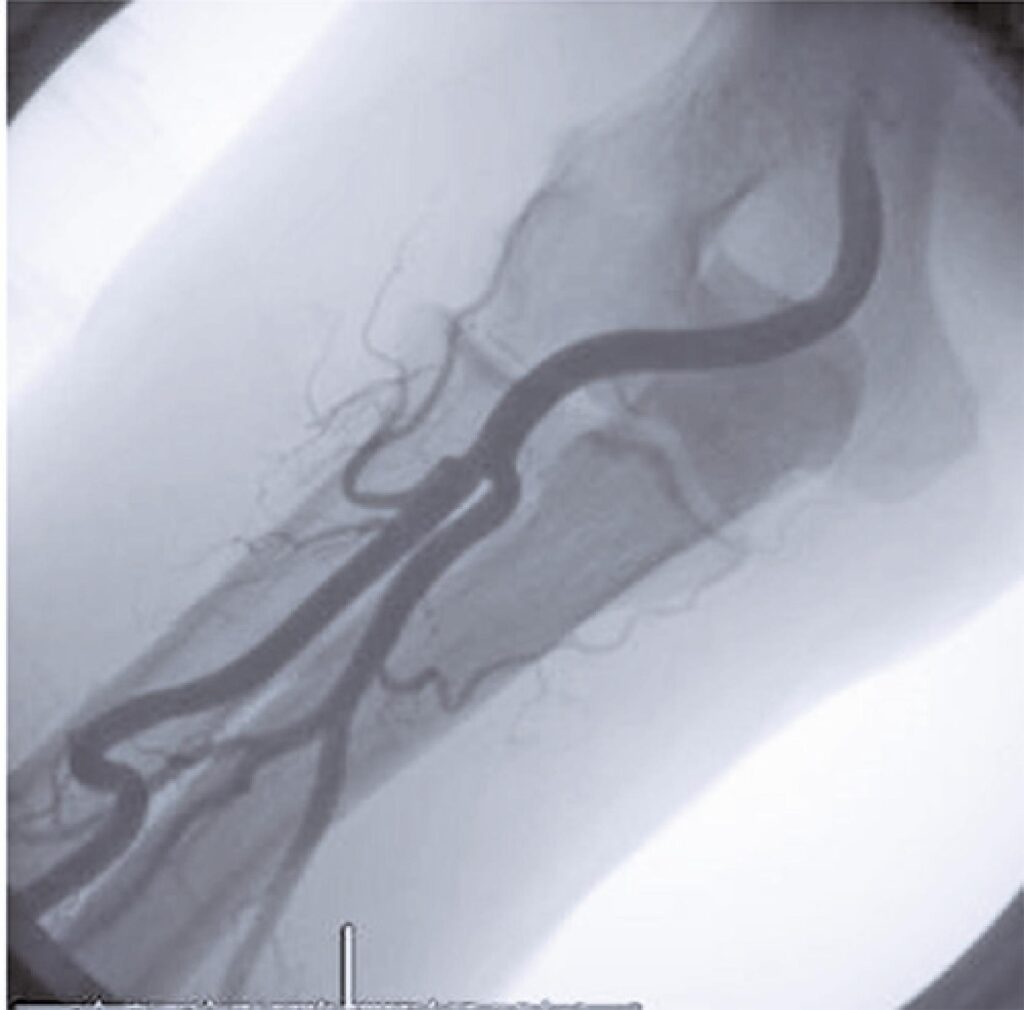

Por meio dos esforços de dedicados intervencionistas, a cateterização do sistema cardiovascular pelo método transradial tem sido reconhecida como o padrão-ouro, devido às várias vantagens a ela associadas, como deambulação precoce e diminuição do sangramento e de várias outras complicações vasculares. Ela se tornou uma alternativa bem-sucedida ao acesso femoral. A vasta experiência dos intervencionistas ajudou na compreensão dos impedimentos anatômicos que podem resultar em diversos problemas técnicos e complicações associadas à abordagem transradial. Não seria justificável a adoção de um método de tentativa e erro pelos intervencionistas em sua curva de aprendizado, à custa de mais falhas no procedimento, complicações e inconveniências para o paciente. O objetivo do presente manuscrito foi examinar todas essas dificuldades e entender o método de tratamento e as várias estratégias preventivas que podem ser usadas para superar as complicações.